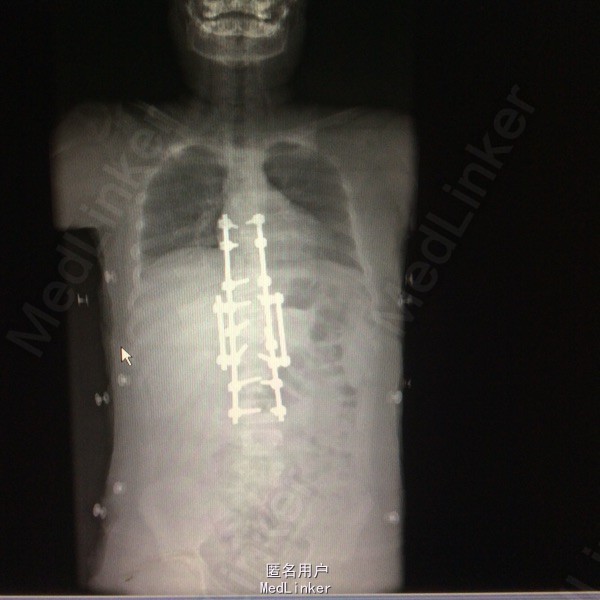

胸椎半椎体畸形 左侧第10肋骨缺如 隐形骶椎裂 双下肢膝外翻 双下肢肌挛缩症 脊柱畸形术,胸5、6、8、9腰1-2-3双侧椎弓根螺钉,去除胸11-12后方椎板,胸12半椎体及上下间隙间盘去除,椎间隙植骨。

本患者后凸可能是由于机制未明的神经肌肉病变,也可能是脊柱矢状位失平衡结果,若是前者导致可能会出现屈伸脊柱的平衡肌群肌张力或肌力增强或减弱,使融合后上下端再次出现冠状面或矢状面失平衡,需再次手术治疗,密切随访患者病情。